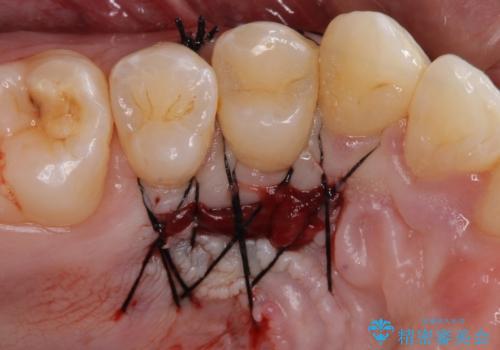

1回目の処置で多少は被覆され歯肉が厚くなりましたが、十分とは言えなかったため、2回目の処置を行いました。

2回目の処置後には十分な厚みと、十分な被覆量を獲得することができました。